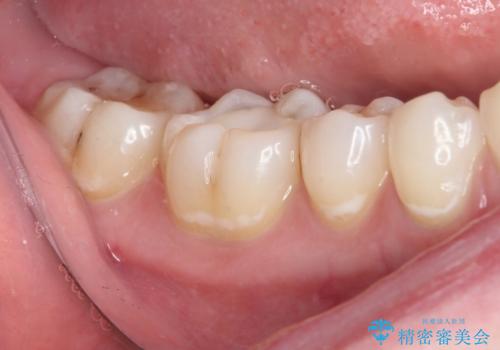

むし歯治療した歯にセラミックを入れたい セラミックインレー修復

- 他院にてむし歯の治療をし、当院にてセラミックを入れたいとのことで来院された患者様です。

むし歯がないか確認し、セラミックインレーにて修復することとしました。

セラミックインレー装着時には、唾液の侵入を防ぐために、ラバーダム防湿を行いました。

見た目、噛み合わせともに満足していただけました。

ラバーダム防湿を行い、セラミックの接着をすることで、唾液や血液などの接着阻害因子を排除することができます。